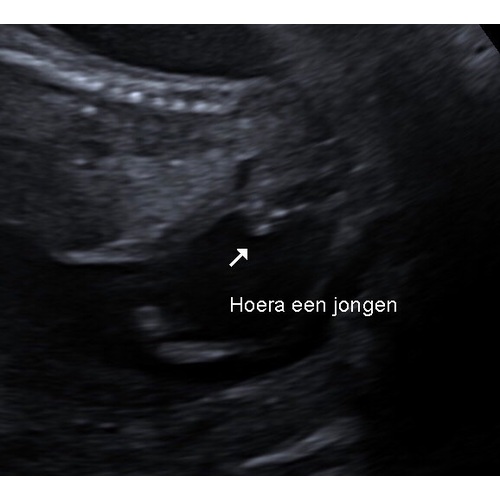

Wij hebben met 15wk geslachtsbepaling gedaan, ons gevoel zei jongen en de echoscopiste zei en zag een jongen. Maar net als met onze dochter (waar ik tot aan de 3D echo met 27 weken heb gevraagd of zij wel echt een meisje is) heb ik twijfel of ze het wel goed gezien heeft en niet per ongeluk de navelstreng voor een pielie heeft aangezien 馃槃 Ik heb 2 ex-collega's waarbij het verkeerd gezien was. Vrijdag de 20 weken echo en ben benieuwd of hij nog steeds een hij is.

Dit is duidelijk een jongetje zo zag het op de echo van mijn zoontje ook uit. 馃槉